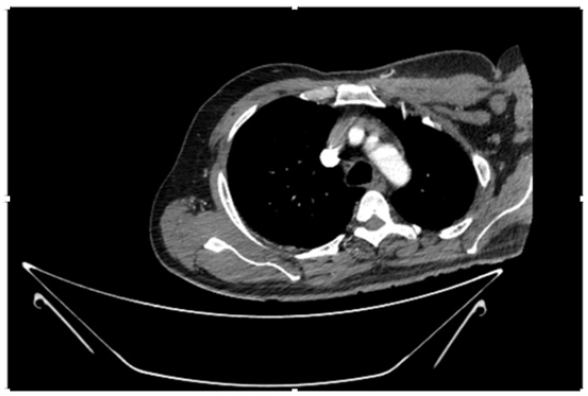

55-years-old chronic smoker had acute, severe pain in the right upper limb for one week; it was cold upto mid arm with skin discoloration. He also noticed numbness and weakness of movement of elbow joint. He underwent below elbow amputation in February 2023 for acute ischemia of left upper limb. He was a current chronic smoker; 15 pack year. General condition was weak; temperature was normal; blood pressure was 100/60mmHg; heart rate was 92/minutes with sinus rhythm; SpO2 was 97% on air; heart was normal. In lower extremities, all peripheral pulses were intact. Local Examination of right upper limb revealed as follows: tenderness; coldness; discoloration; decreased motor function and sensory modalities. Axillary, brachial and radial pulses were not palpable. Hand-held Doppler failed to detect any signal in arterial system; therefore, we arranged for emergency embolectomy. complete occlusion of right upper limb arterial system Full blood count showed high hemoglobin (14.6gm%); normal total WBC and platelet count. Coagulation profile was normal. Parenteral unfractionated heparin, antibiotics, tramadol, proton-pump inhibitors, anti-platelets and HMG CoA reductase inhibitors were given. Doppler ultrasound demonstrated complete occlusion of right upper limb arterial system. CT Angiogram illustrated occlusion of subclavian artery downwards on both sides. Figures 1-14 shows complete occlusion of right subclavian artery without collaterals. On Day ‘2’ of admission, the patient passed black tarry stool for 3 times. However, the vital signs were stable; blood pressure was 100/60mmHg; heart rate was 92/min; SpO2 was 97% on air; the abdomen was soft and not tender. Above elbow amputation was done on Day ‘2’ of admission. Intra-operative findings were as follows: (1) no active bleeding at brachial artery; (2) thrombosis along brachial artery; (3) muscle color and consistency were not healthy.

Figure 4: CT Angiogram at neck showing normal brachio-cephalic trunk, common carotid artery, and narrow right subclavian artery.

Figure 5: CT Angiogram at neck showing normal brachio-cephalic trunk, common carotid artery, and narrow right subclavian artery.

Figure 6: CT Angiogram at neck showing brachio-cephalic trunk, common carotid artery and narrow right subclavian artery.

Figure 7: CT Angiogram at neck showing brachio-cephalic trunk, common carotid artery and narrow right subclavian artery.

Figure 10: CT Angiogram at upper arm showing totally occluded right axillary artery; normal internal carotid artery and external carotid artery.